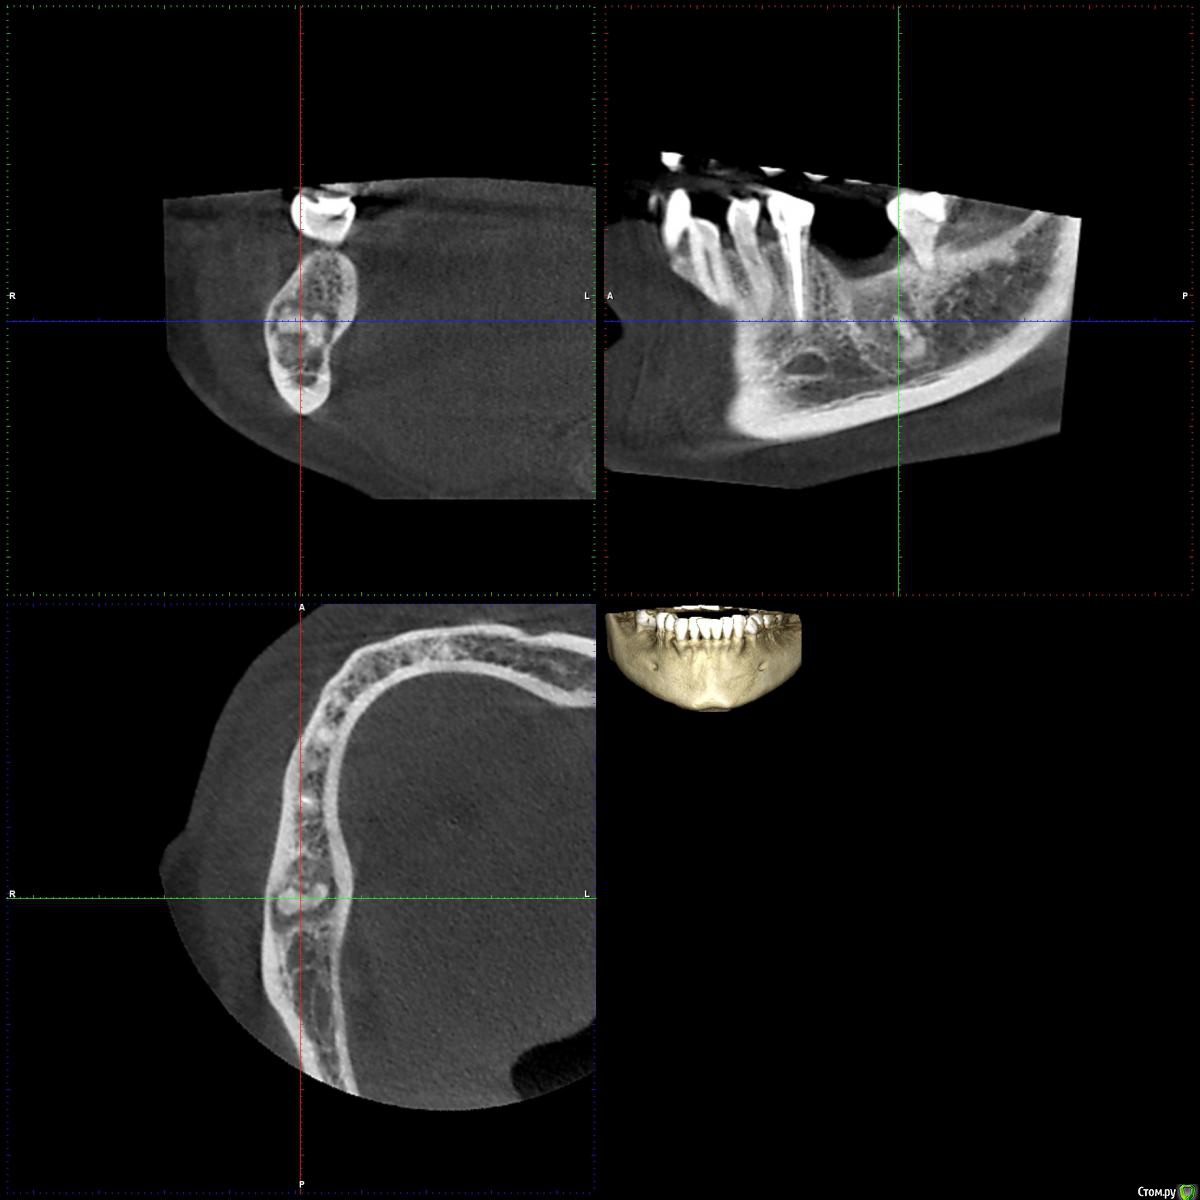

L.E.S.I.K. Опубликовано 29 мая, 2017 Поделиться Опубликовано 29 мая, 2017 Коллеги, нужна помощь. Обратилась пациентка с желанием поставить имплант в область 46 зуба. На орто и КТ вот такая картина. Не могу понять это остаток корня, зона остеосклероза...? Лучше удалять или не лезть и поставить имлант рядом? Ссылка на комментарий

dok1 Опубликовано 29 мая, 2017 Поделиться Опубликовано 29 мая, 2017 (изменено) Не вижу сложности. Отслоиться с вестибуляра. Окно сбоку. Работа как при резекции вк. Потом в обычном режиме сверху имплант. Графт сбоку и с фдм ушиться. Протезирование через 2-3 месяца. Получится как-бы синуслифт открытый, только снизу Изменено 29 мая, 2017 пользователем dok1 4 Ссылка на комментарий

dok1 Опубликовано 29 мая, 2017 Поделиться Опубликовано 29 мая, 2017 Убирать этот корень обязательно. Ибо в оболочке он. Неанкилозированный. Ссылка на комментарий